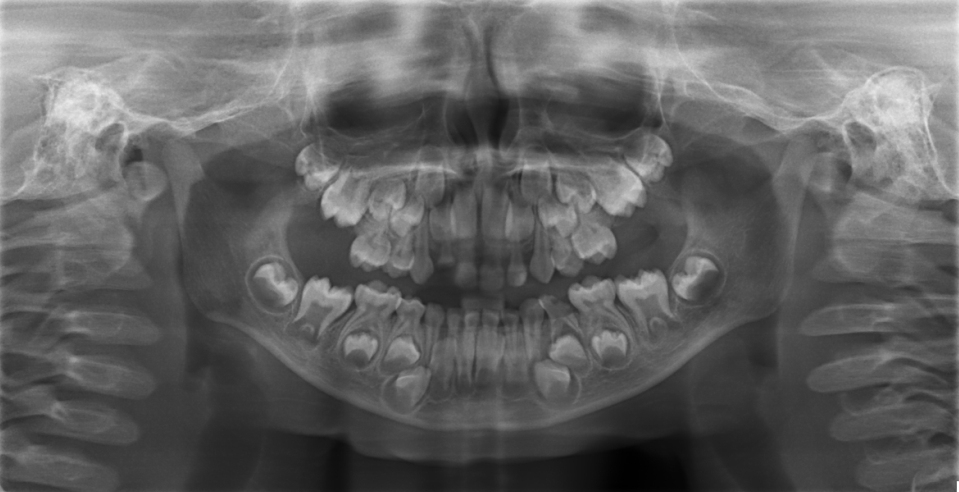

Intraoral examination revealed presence of grossly decayed #74,#52 and dental caries extending into the pulp in relation of #64.Panoramic radiograph confirmed chronic irreversible pulpitis in relation to #64 [Table/Fig-3] and treatment plan was formulated and explained to the parents. Pediatrician referral was made keeping in view the patient’s medical status.

Panoramic radiograph showing grossly decayed #52, #74 and chronic irreversible pulpitis in relation to #64